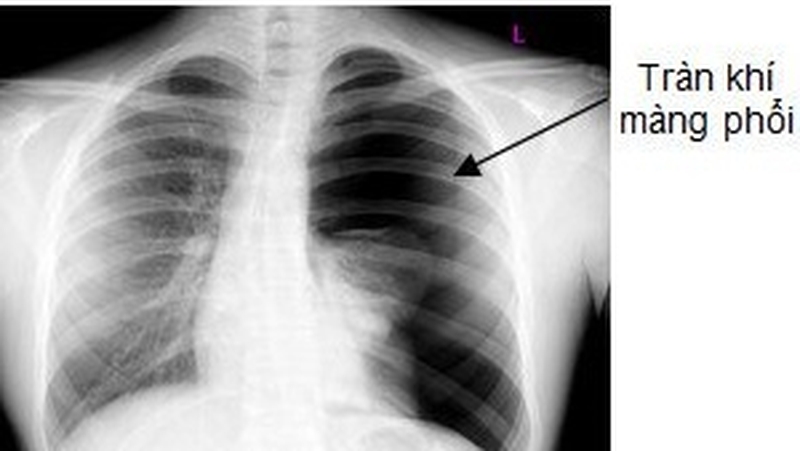

Thực hiện chụp X Quang phổi và quan sát:

• Khoảng tăng sáng, mất hình nhu mô phổi, hình đường viền ngăn giữa nhu mô phổi và vùng tràn khí.

• Khoang liên sườn giãn rộng.

• Trung thất bị đẩy lệch sang bên đối diện trong trường hợp tràn khí màng phổi áp lực dương.